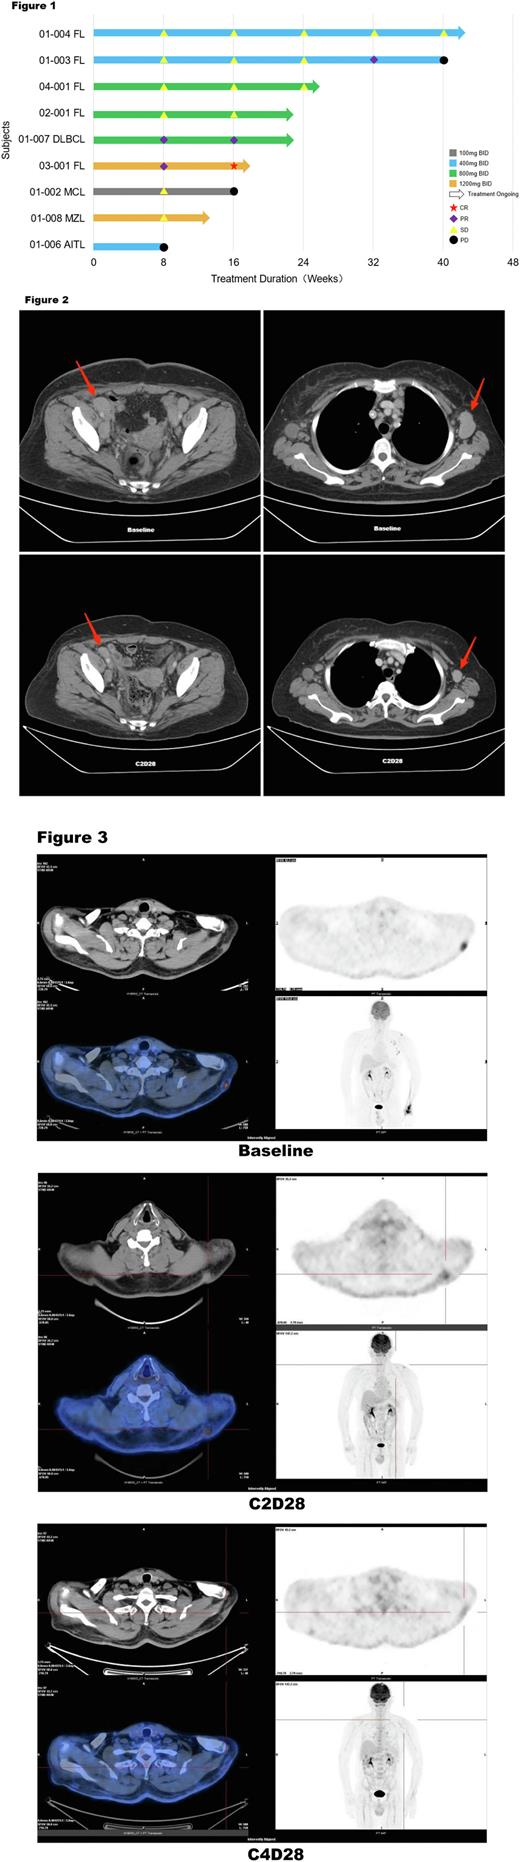

Results: In the dose-escalated phase, as July 15, 2022 , a total of 15 pts were enrolled and treated with 5 dose groups of XNW5004 (from 100 mg to 1600 mg BID). The median age was 58 years (range, 47-71). Pts received a median of 3 (range, 2-7) prior lines of treatment and diagnoses of diffuse large B-cell lymphoma (DLBCL, n = 3), follicular lymphoma (FL, n = 6), mantle cell lymphoma (MCL, n = 1), marginal zone lymphoma (MZL, n = 2), small lymphocytic lymphoma (SLL, n = 1), angioimmunoblastic T-cell lymphoma (AITL, n = 1), and Waldenström macroglobulinemia (WM, n = 1). XNW5004 had a favorable safety and tolerability, and no dose-limiting toxicity (DLT) was observed at doses up to 1600 mg BID. Grade 3 treatment-related adverse events (TRAEs) occurred in 4 (26.7%) pts, including white blood cell decreased, neutrophil count decreased, lymphocyte count decreased, and platelet count decreased. No grade ≥4 adverse events (AEs) and serious TRAEs occurred. Any grade TRAEs in ≥20% of pts included nausea (33.3%), diarrhea (33.3%), alanine aminotransferase increased (26.7%), neutrophil count decreased (26.7%), white blood cell decreased (26.7%), hypertriglyceridemia (26.7%), aspartate aminotransferase increased (20%), vomiting (20%), blood lactate dehydrogenase increased (20%), blood bilirubin increased (20%), pruritus (20%), anemia (20%). With a median follow-up of 4 (range, 2-10) cycles, the objective response rate (ORR) was 33.3%, and the disease control rate (DCR) was 78% in the 9 evaluable pts. The median progression-free-survival (mPFS) and median duration of response (mDOR) were not reached. Among pts with EZH2 wild-type (WT) FL (n=5) , the ORR was 40%, the DCR was 100%, the mPFS and mDOR were not reached. In all pts with stable disease (SD), the lesions continued to shrink. One patient (Figure 2) with DLBCL (non-GCB) received 2 cycles of XNW5004, the lesions were reduced by 59.8%; and after 4 cycles of treatment, the lesions were reduced by more than 70%. One patient (Figure 3) with FL (EZH2 WT) received 2 cycles of XNW5004, the subcutaneous lesions and axillary lymph nodes were significantly reduced, PET-CT showed that uptake was strongly reduced, and the Deauville score (DS) was 5 and 3, respectively. The efficacy evaluation was partial response (PR). After 4 cycles of treatment , PET-CT showed that the metabolism of subcutaneous lesions and axillary lymph nodes continued to decrease, the DS was 2 and 1, respectively, and the efficacy evaluation was complete response (CR). In addition, the PK of XNW5004 was well.